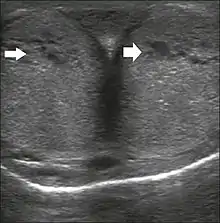

Transverse ultrasound image, ventral view of the penis. Image obtained after induction of an erection, 15 min after injection of prostaglandin E1, showing dilated sinusoids (arrows).[45]

Penile ultrasonography with doppler can be used to examine the erect penis. Most cases of ED of organic causes are related to changes in blood flow in the corpora cavernosa, represented by occlusive artery disease (in which less blood is allowed to enter the penis), most often of atherosclerotic origin, or due to failure of the veno-occlusive mechanism (in which too much blood circulates back out of the penis). Before the Doppler sonogram, the penis should be examined in B mode, in order to identify possible tumors, fibrotic plaques, calcifications, or hematomas, and to evaluate the appearance of the cavernous arteries, which can be tortuous or atheromatous.[45]

Erection can be induced by injecting 10–20 µg of prostaglandin E1, with evaluations of the arterial flow every five minutes for 25–30 min (see image). The use of prostaglandin E1 is contraindicated in patients with predisposition to priapism (e.g., those with sickle cell anemia), anatomical deformity of the penis, or penile implants. Phentolamine (2 mg) is often added. Visual and tactile stimulation produces better results. Some authors recommend the use of sildenafil by mouth to replace the injectable drugs in cases of contraindications, although the efficacy of such medication is controversial.[45]